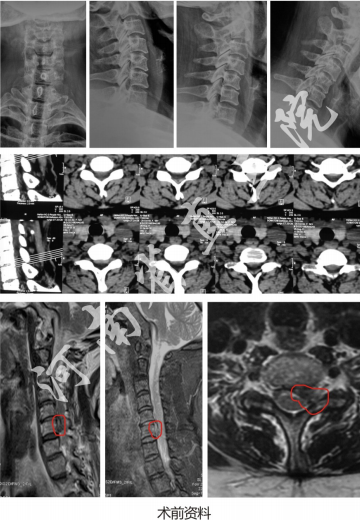

神经根型颈椎病(脱出游离型)

患者:李XX,女,56岁

主诉:颈肩部伴左上肢疼痛伴活动受限1周。

查体:C5-6-7左侧椎旁压痛,左侧臂丛牵拉试验阳性,屈颈试验阳性,双上肢肌力肌张力正常。

诊断:神经根型颈椎病(脱出游离型)